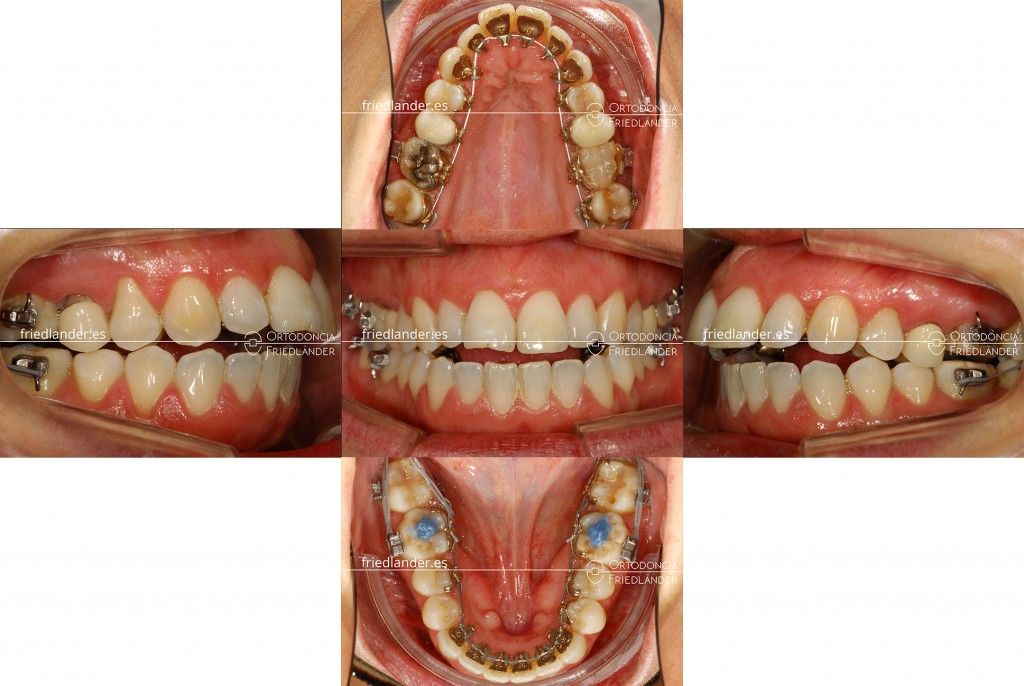

En la primera visita la paciente nos expuso sus preocupaciones; no le gustaba la estética de sus dientes apiñados y nos comentaba que no podía morder bien. En la primera exploración clínica podemos ver unas arcadas estrechas, apiñamiento inferior moderado y una tendencia a la mordida abierta anterior. A nivel funcional la paciente presenta una deglución atípica (la lengua empuja los dientes hacia fuera). La paciente escogió tratarse con ortodoncia lingual invisible ya que no quería que se vieran los aparatos en ningún momento.

A los 5 meses de tratamiento podemos ver que, efectivamente, la mordida se abrió y la mandíbula se fue hacia atrás.

Estos efectos iniciales del tratamiento ya estaban previstos gracias al estudio minucioso del caso, por lo que procedemos a la colocación de 4 microtornillos en las zonas retro molares; los inferiores para retraer ligeramente la arcada inferior y los superiores para intruir y distalar los molares superiores (subir y llevar hacia atrás las muelas superiores) y así cerrar la mordida abierta.